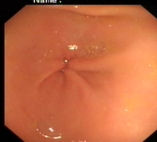

内镜下表现:黏膜红白相间,以白色为主,黏膜皱襞变平或消失,部分黏膜血管显露,可伴有黏膜颗粒或结节状等表现。如伴有肠化生于电子染色窄带成像放大内镜(NBI ME)下发现胃粘膜上皮细胞表面的脑回样结构嵴部的纤细浅蓝色线样结构。病理活检可进一步确诊。

正常胃表现

萎缩胃表现